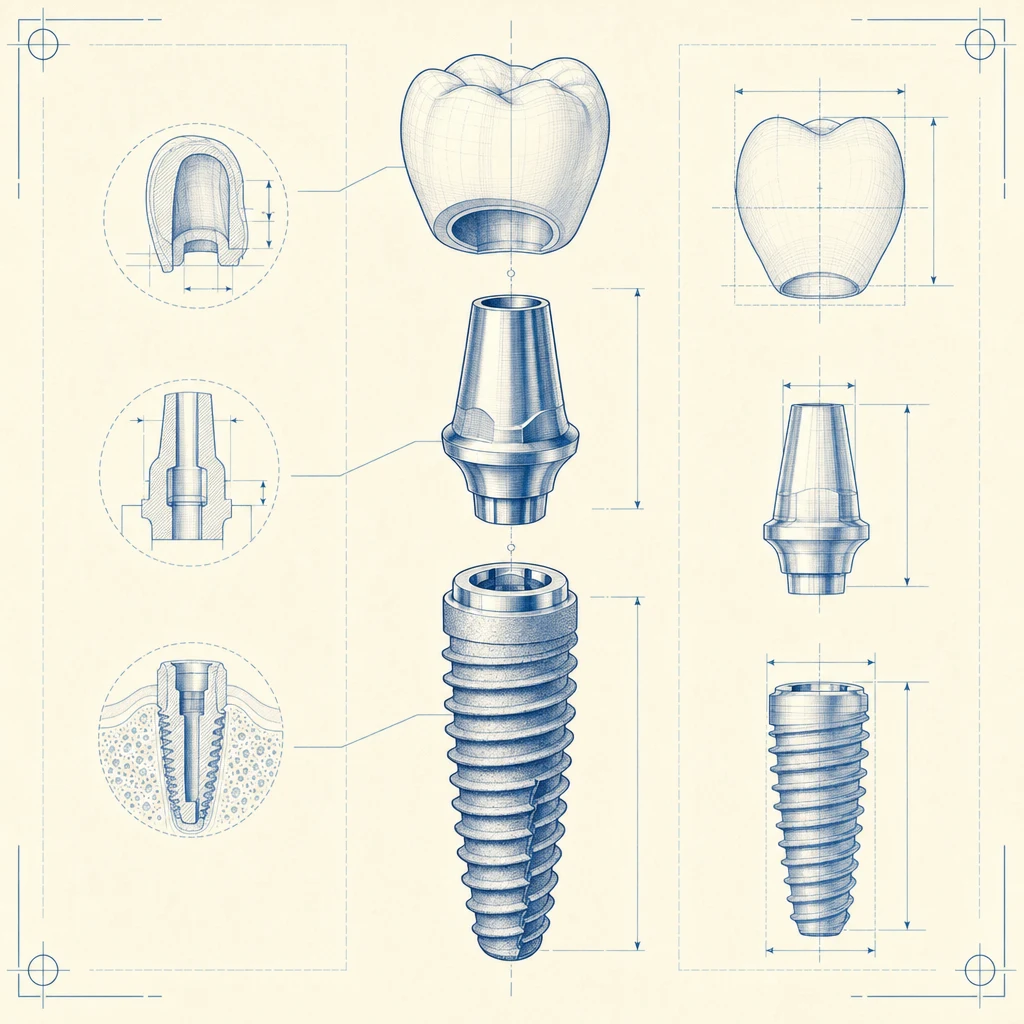

기본 구성

- 픽스처(인공뿌리): 제조사·재질에 따라 가격대가 분명히 다릅니다. 국산·해외 프리미엄 브랜드 차이가 큽니다.

- 어버트먼트(연결부): 픽스처와 보철을 잇는 부품

- 보철물(크라운): 보이는 부분. 메탈 < PFM < 지르코니아 < 올세라믹 순으로 가격이 올라가지만 심미성·내구성도 함께 향상